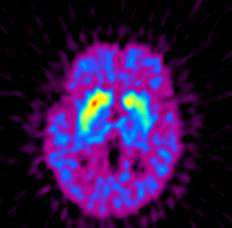

图1,正常人,碳11-CFT显像,双侧纹状体显示正常